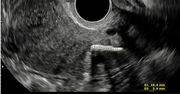

Prawdopodobnie jest najmłodszą pacjentką z tym nowotworem. U Peyton Linafelter z Kolorado w Stanach Zjednoczonych raka jajnika w czwartym stadium lekarze zdiagnozowali niemalże w dzień jej 16. urodzin. Był kwiecień 2016 roku, a nastolatka właśnie zaczynała pracę jako modelka. Mimo to głośno wyznała, że cierpi na nowotwór, który dawał już przerzuty na płuca i żołądek. Lekarze dawali jej 17 proc. szans, że przeżyje najbliższe pięć lat. Dziś wiadomo, że dziewczyna jest zdrowa. Nie wstydzi się przyznać, że cierpiała na nowotwór i prosi kobiety, by regularnie się badały.